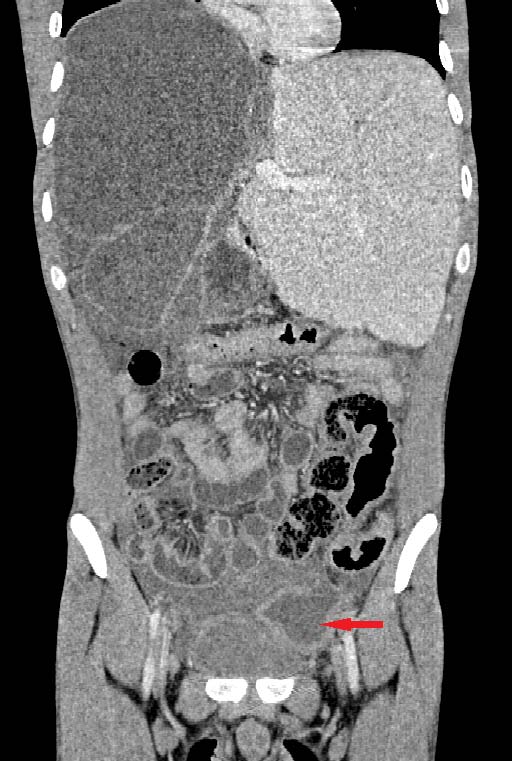

Histology is similar to hamartomas, although some state a lymphangiectasic or neoplastic nature, without any malignant potentiality [3]. Ultrasonography documents mono-or multiloculate fluid-superfluid lesions with a substantial lack of flow with Doppler mode (figure/patient 1-2). Computer Tomography (CT) describes low attenuation masses with occasional fluid level and minimum septal and peripheral enhancement. Magnetic resonance imaging (MRI) detects iso-or hyposignal on T1-weighted sequences and hyper-signal on T2-weighted sequences, a halo of enhancement around the septa of macro-cystic lesions and peri lesional lymphoedema (figure/patient 2-3) [4].

Sclerotherapy is nowadays largely employed in case of macro-cystic or mixed lymphangiomas, where the size of the cysts allows them to be punctured and a wider distribution of the agent is achieved. However, OK-432, bleomycin and above all doxycycline have recently proved effective also with micro-cystic variety [2]. The rationale comes from the observation that lymphangiomas can reduce their size or regress after a spontaneous infection, probably due to the destruction of the epithelium, reduction of lymph production and collapse of the cyst: thus, the idea of adopting sclerosing agents to mimic such an effect. Puncture of the dominant cyst (or more, in case they are noncommunicating) with a fine needle (20 G or more) is followed by aspiration (in order to enhance the SA effect) and injection, in one or more times, of the sclerosing agent, using the same amount as the aspirated fluid (if impossible, half of the lesion's volume). It can be repeated in case of partial response or whenever more administrations are chosen, each session being separated by weeks up to a month. General or loco-regional anaesthesia is preferred in children or uncooperative patients and in adults or small cystic malformations, respectively; the patient's position is changed many times to favour a uniform distribution of the agent and the treatment lasts up to two hours. A postoperative compressive bandage is advised in order to increment the time of contact between the solution and the cyst's wall and to prevent seroma formation, bleeding or effusion of the SA. The procedure can be performed under ultrasound or CT: the first is cheaper, more available, does not employ ionising radiations (thus being advisable in children and young adults), defines better the different components within the lesion, grants different cranio-caudal angles and reduces the risk of accidental puncture of large blood vessels; however, it is operator-dependent and offers a narrow field of view, with the risk of missing some important findings, especially at the post-procedure check. CT instead is easier to perform and provides a more panoramic view but implies radiation and the needle path to lie on the axial plane with its full length [1]; a detailed example of this procedure is offered in figure (patient) 4, whereas figures (patients) 5 and 6 show examples of successful outcomes comparing lymphangiomas before and after sclerotherapy. Fluoroscopic guidance is also reported, especially in case of the most superficial lesions, with the possibility to inject contrast medium into the lesion in order to highlight communications between the intra-lesional spaces and establish the amount of SA to be used [4]. Complications include intraoperative bleeding (due to their dysplastic nature), accidental injuries to nerves, vessels, organs and other tissues (due to extravasation), peri-lesional fibrosis and aesthetic sequelae (due to necrosis followed by second-intention reparation), dosedependent cardio-pulmonary toxicity (especially with bleomycin) and acute respiratory insufficiency (with large lymphangiomas undergoing inflammation, necrosis and quick volumetric expansion); the latter could be managed with dexamethasone or, preferably, avoided by splitting the treatment in more sessions [7]. An example of follow-up program would consist of a clinical examination after one to three weeks, ultrasonography after six to twelve weeks and then (depending on the results of ultrasound) MRI, unless evidence of early recurrence or any other complication occurs [8]. A review by Adams et al didn't prove the superiority of sclerotherapy over surgery but showed it was the treatment of choice in most major paediatric vascular anomaly centres: surgery was reserved for refractory cases, with sclerosing agents not improving either clinics or aesthetics, micro cystic lesions or those associated with life-threatening airway obstruction. Nowadays there are no worldwide-accepted guidelines and patient selection seems to guide the choice. In addition, neither surgery nor sclerotherapy can guarantee complete healing with just one session: it is actually advisable to perform multiple treatments or combine them [1].